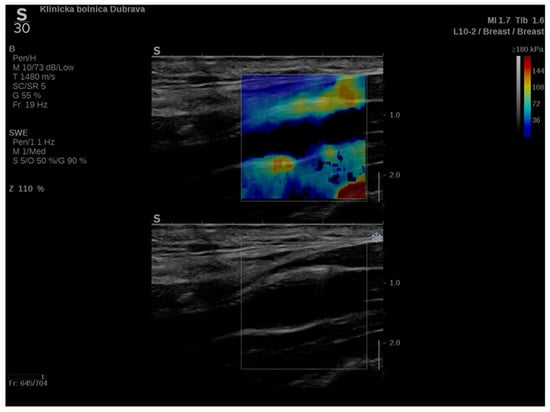

In addition to conventional, Doppler and contrast-enhanced ultrasonography, elastography techniques are another area where ultrasound is being increasingly used, this time to assess the elastic properties of the insonated tissue. There are two types of ultrasound elastography: strain and shear wave elastography (SWE). Strain elastography is performed by manual compression using the transducer, which then produces an image based on the resulting displacement of the tissue caused by the compression. However, it is difficult to measure the exact amount of the applied force during compression, resulting in the method being difficult to standardize. Additionally, the absolute elasticity values cannot be calculated, and only qualitative results can be obtained. Unlike strain elastography, SWE is a type of ultrasound elastography where the elastic properties of the insonated tissues can be expressed both qualitatively and quantitatively (Figure 1 and Figure 2) [22].

Figure 1. An example of an ultrasound examination with shear wave elastography of a segment of the distal right CCA in the longitudinal view with B-mode ultrasound at bottom and shear wave elastography at the top where the elastic properties of the examined tissues (carotid artery wall and surrounding soft tissues) are displayed qualitatively by benign color-coded and superimposed on the B-mode image. Red color denotes the stiffest areas with the highest elastic modulus values.